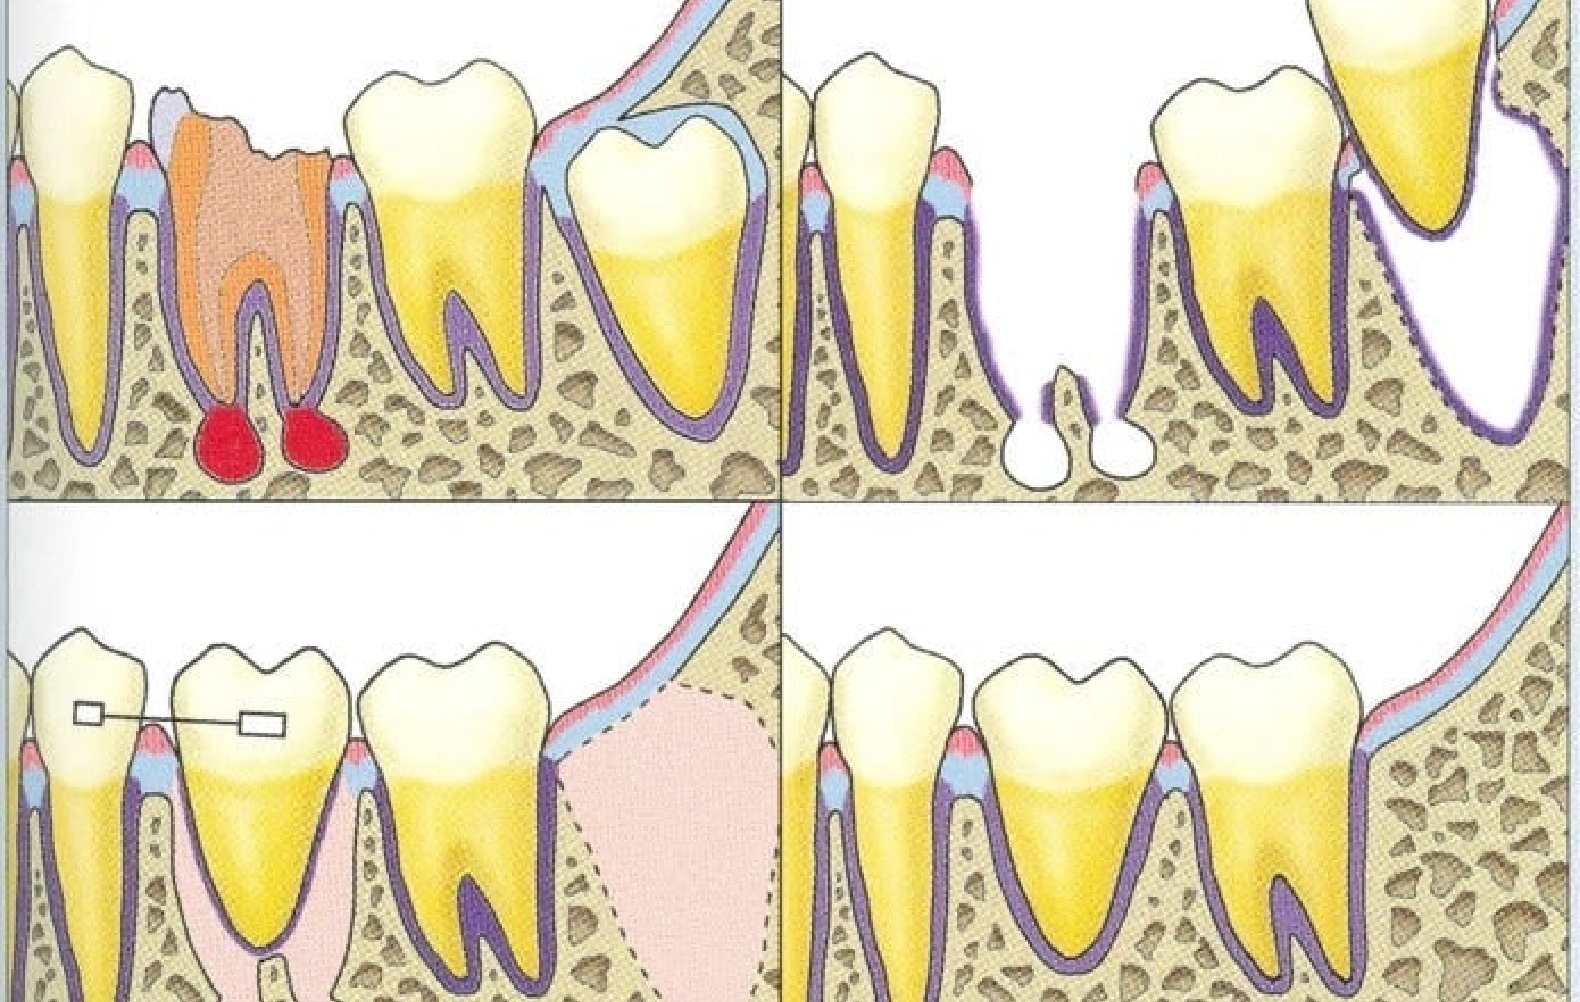

親知らずや埋伏歯など、噛み合わせに関与しない歯を抜歯予定部位へ移す治療です。

歯根膜ごと移植することで骨や歯ぐきと自然に馴染み、咬合圧や食感を繊細に感じ取れる点が最大の特徴です。

1950〜60年代にはすでに臨床報告があり、虫歯で失った第一大臼歯へ根未完成の智歯を移植する試みが行われていました。その後、1970年代以降の組織学・病理学研究により、歯根膜を守ることこそ成功の鍵とする生物学的原則が確立されました。

歯を抜いたその日に移植する「抜歯即時移植」が最も治癒に有利です。

抜歯窩の側壁に残る歯根膜が活性化し、治癒を促すためです。ただし次のようなケースでは、数週間待ってからの早期移植を選択します。